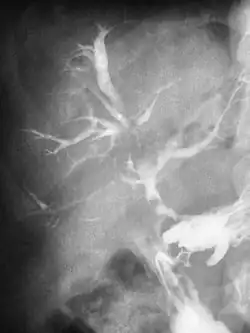

Свищ, или фи́стула (от лат. fistula «трубка»), — канал, соединяющий полости тела (в том числе патологические) или полые органы с внешней средой или между собой. Обычно имеет вид узкого канала, выстланного эпителием или грануляционной тканью.

- Бронхиальный свищ — патологическое сообщение просвета бронха с плевральной полостью[5]